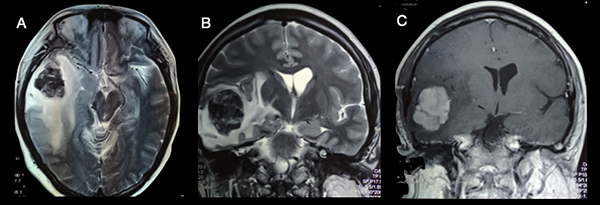

Luego de la cirugía, la paciente no agregó ningún déficit neurológico con un valor en la escala de Rankin modificada igual a 1. Fue externada cuatro días después de la intervención. En controles ambulatorios se solicitó RMN postoperatoria (Figura 4), en la cual se evidencia resección completa de la lesión asociado a cambios postoperatorios.

Figura 4

: A) RMN T2 corte axial, B) T2 corte coronal, C) T1 con contraste en todas las secuencias se puede apreciar la exéresis completa de la lesión, con la restauración de la línea media y la ausencia de edema.